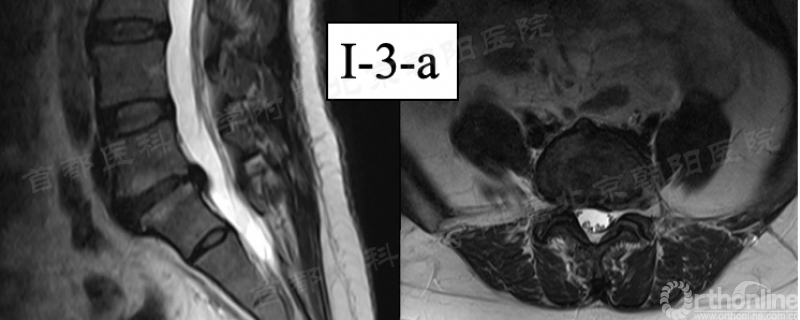

b. 第91例,第一次神经损伤,也希望是最后一例。

第91例,L2/3节段I-2-a区LDH。在置管后患者诉左下肢屈髋较对侧无力,无下肢放射痛及麻木,术中透视如图(红框)所示。镜下摘除髓核后将工作通道朝向背侧观察神经,患者诉颈部疼痛(脊髓高压症),镜下发现硬膜缺损(红箭头),但神经结构完整。立即结束手术。术后髂腰肌肌力IV级,大腿前方感觉减退,术后复查CT显示L3上关节成型后游离骨块导致出口神经受压。